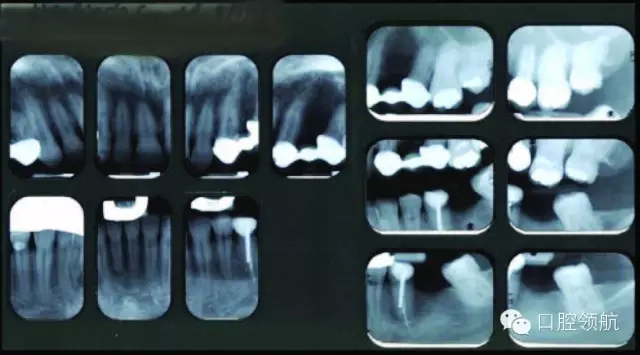

● 未見明顯的松動度或者創(chuàng)傷牙合(圖3)。

圖3 上頜左側(cè)后牙的影像學(xué)檢查。